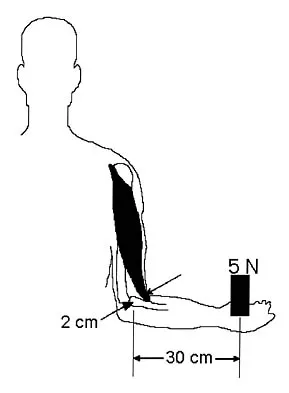

Question 64

Figure 6 shows an object being held in an outstretched hand. To offset the moment created by the object (ignoring the weight of the forearm), the biceps must generate a force of

Explanation